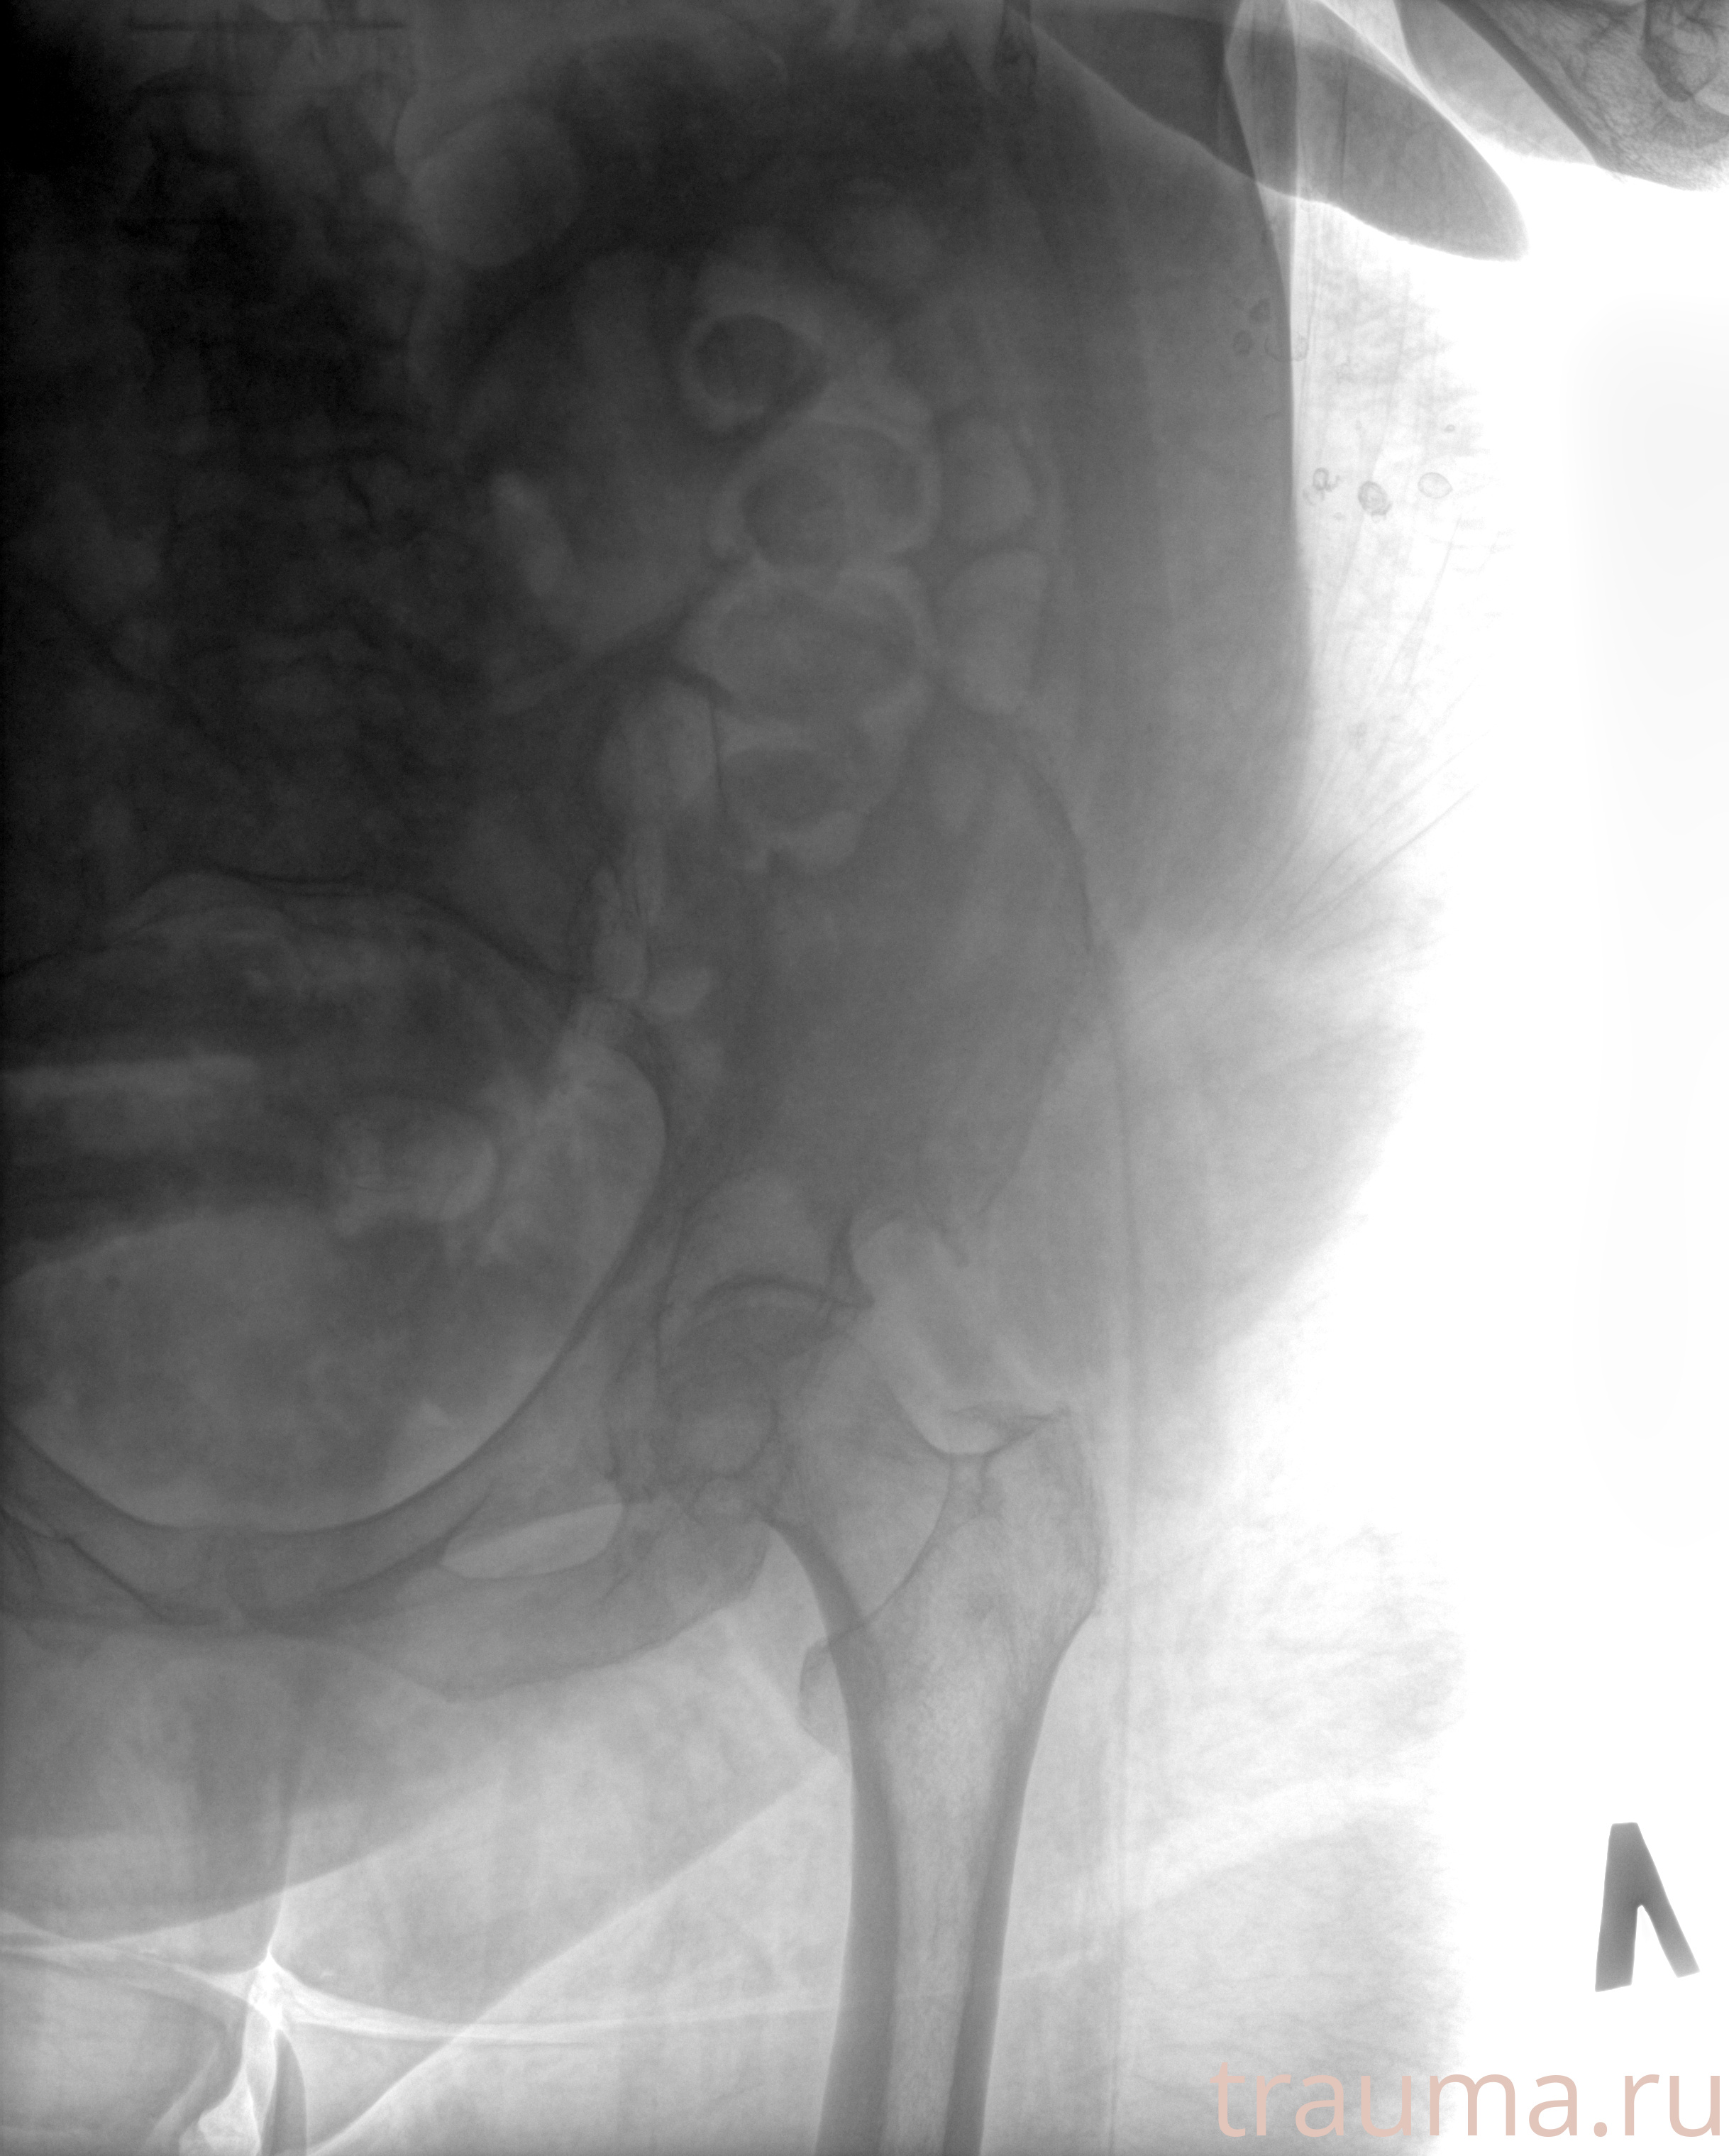

Рентгенограммы

Рентген на дому: по вашему адресу приезжает врач-рентгенолог, травматолог-ортопед с мобильным рентгеновским аппаратом, проводит диагностику травмы или заболевания, делает необходимые рентгенограммы, дает рекомендации по дальнейшему лечению. Получить качественные снимки в домашних условиях возможно благодаря уникальной методике, разработанной МосРентген Центром для института  Склифосовского